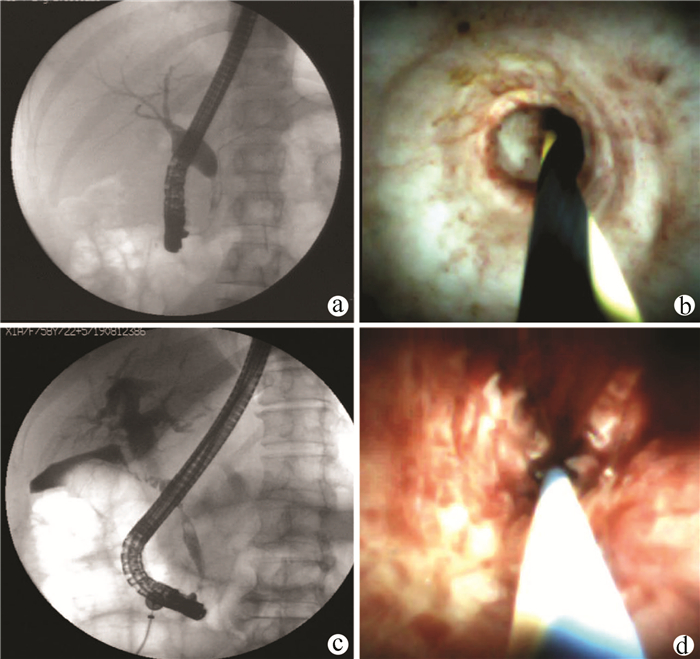

Massive hemorrhage caused by total gastrointestinal varices and recurrent heterotopic varices due to portal vein tumor: A case report

Qin LIU, Heye LIANG

2021, 37(10): 2414-2416. DOI: 10.3969/j.issn.1001-5256.2021.10.032

Abstract(787) HTML (348) PDF (3571KB)(67)

Abstract: